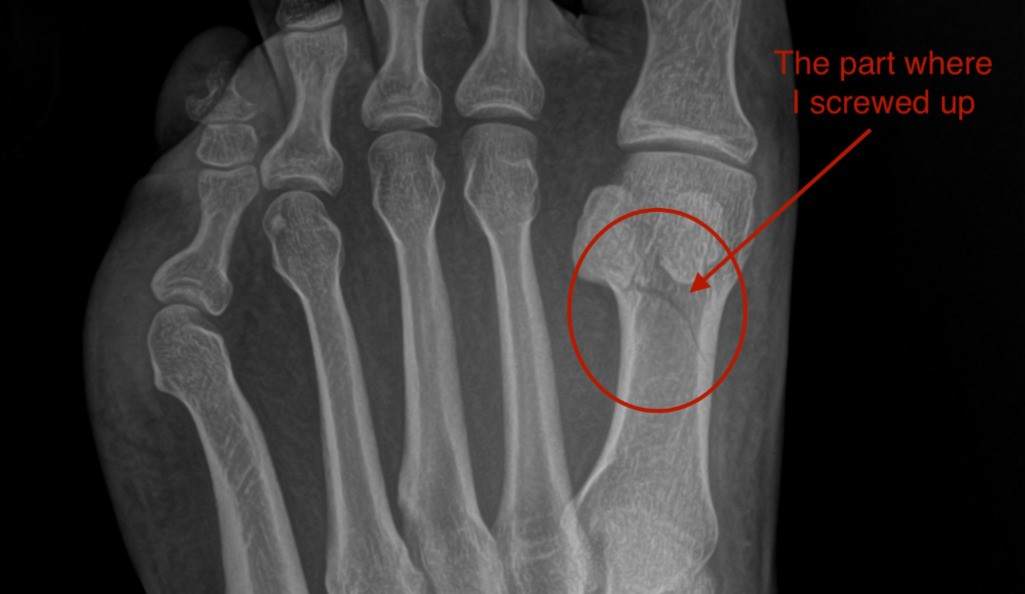

可及性:这种配置的可视化特性对视力正常的人有利,但尽管有排他性,但VR可以根据需要把东西做大,或者管理对比度和光线,为有视觉缺陷的人提供计算机可用性方面的改进。你也可以采用非传统的座椅或书桌(或床)配置,去适应各种行动不便或身体有困难的人。我在开始全天候VR工作的几个月后,遭遇了脚部多处骨折,需要四个月不得承重,而且前两个月需要把脚抬高。这种情况下已经不适合坐在办公桌前,有那么好几个星期,客厅的躺椅变成我唯一的选择。在那些日子里,笔记本电脑、头显以及多显示器设置就足以让我可以应付自如。

左脚第一跖骨骨折的X光片